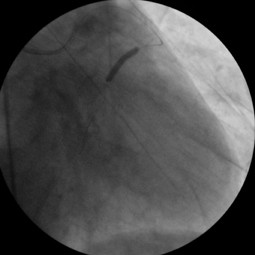

Fig. 3

Vidoe 2. Thrombolysis In Myocardial Infarction -3 flow was ensured (avi 1,1MB)